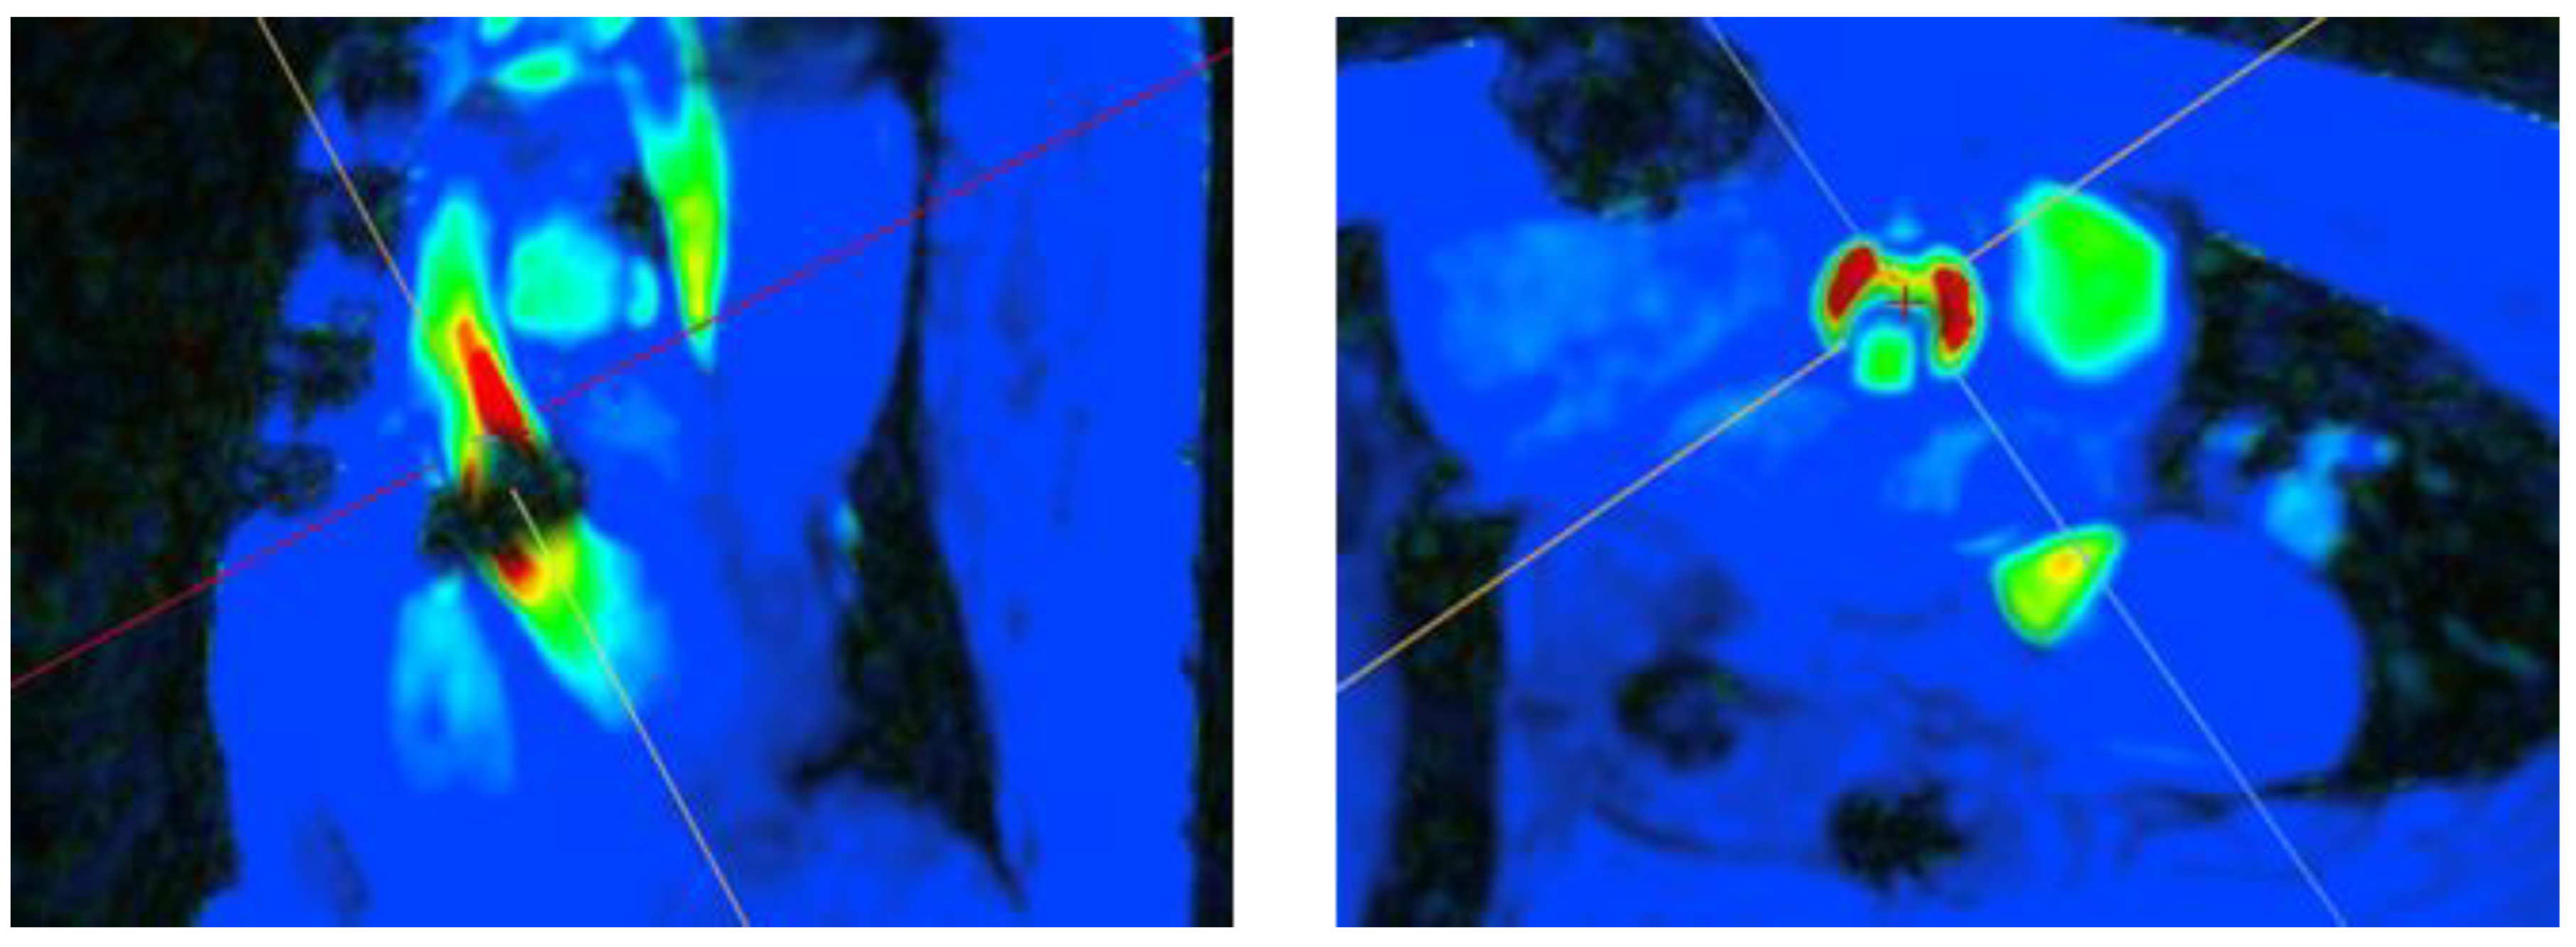

- 2D-PC

- 4D-flow